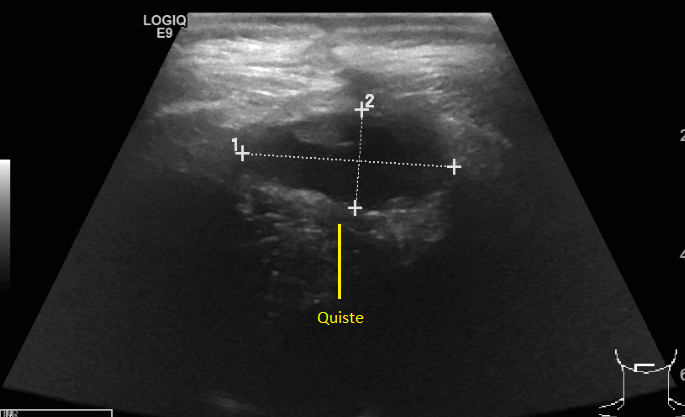

El 13 de diciembre tuve mi primer control fuera del hospital, previo a la cita, me saqué una tomografía y el ultrasonido. El doctor quería ver si el quiste redujo su tamaño, y así fue pero me pidió seguir con la medicina para el cerebro y el vendaje, del acné me dijo que iba a tardar algunos meses, lo mismo que la retención de líquidos, que no me preocupara por el peso ya que en unos meses, mi cuerpo eliminaría esos kilos de manera natural. Lo que no le gusto fue mi semblante, estaba demasiado pálida y amarilla así que me mando estudios.